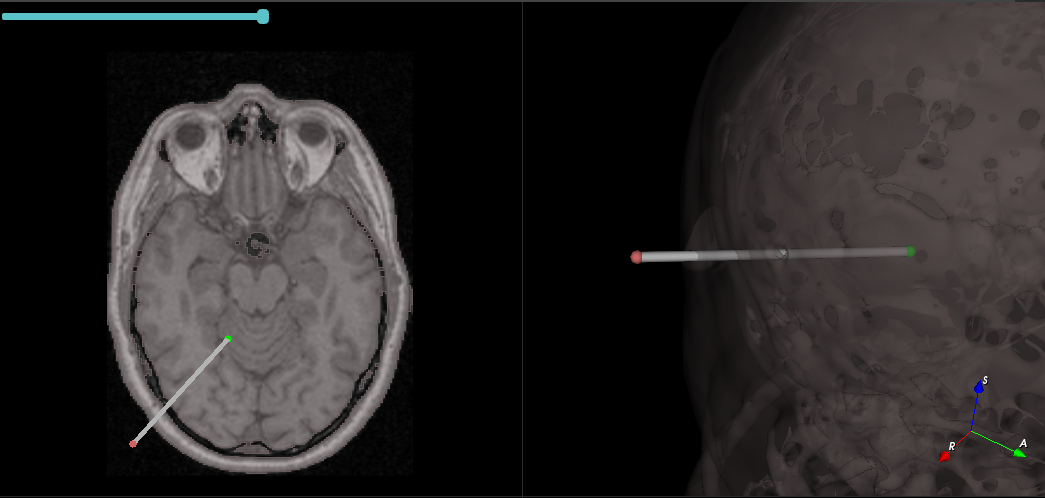

The NousNav project is an initiative led by Dr Alex Golby to develop a low-cost neuronavigation system designed for use in low- and middle-income countries. We are developing a 3D Slicer based application focused on supporting segmentation, registration and navigation tasks.

Recorded and edited a ~2-min video showcasing the complete Planning, Registration and Navigation workflow. See video

| Click on the image below to see the video |